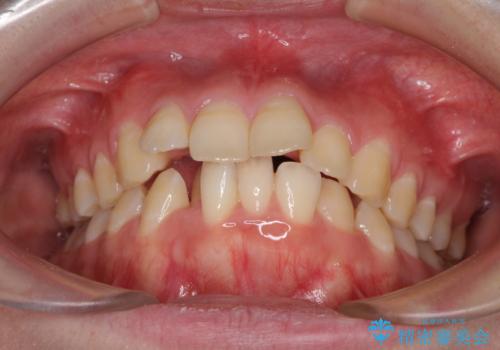

- 上の前歯の出っ歯とでこぼこの歯並びを気にして来院された患者様です。

口元を積極的に引っ込めるために、上下左右の小臼歯4本を抜歯することとしました。